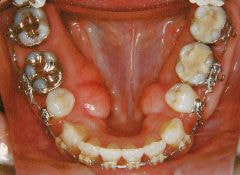

治療例2 (補綴処置+矯正)